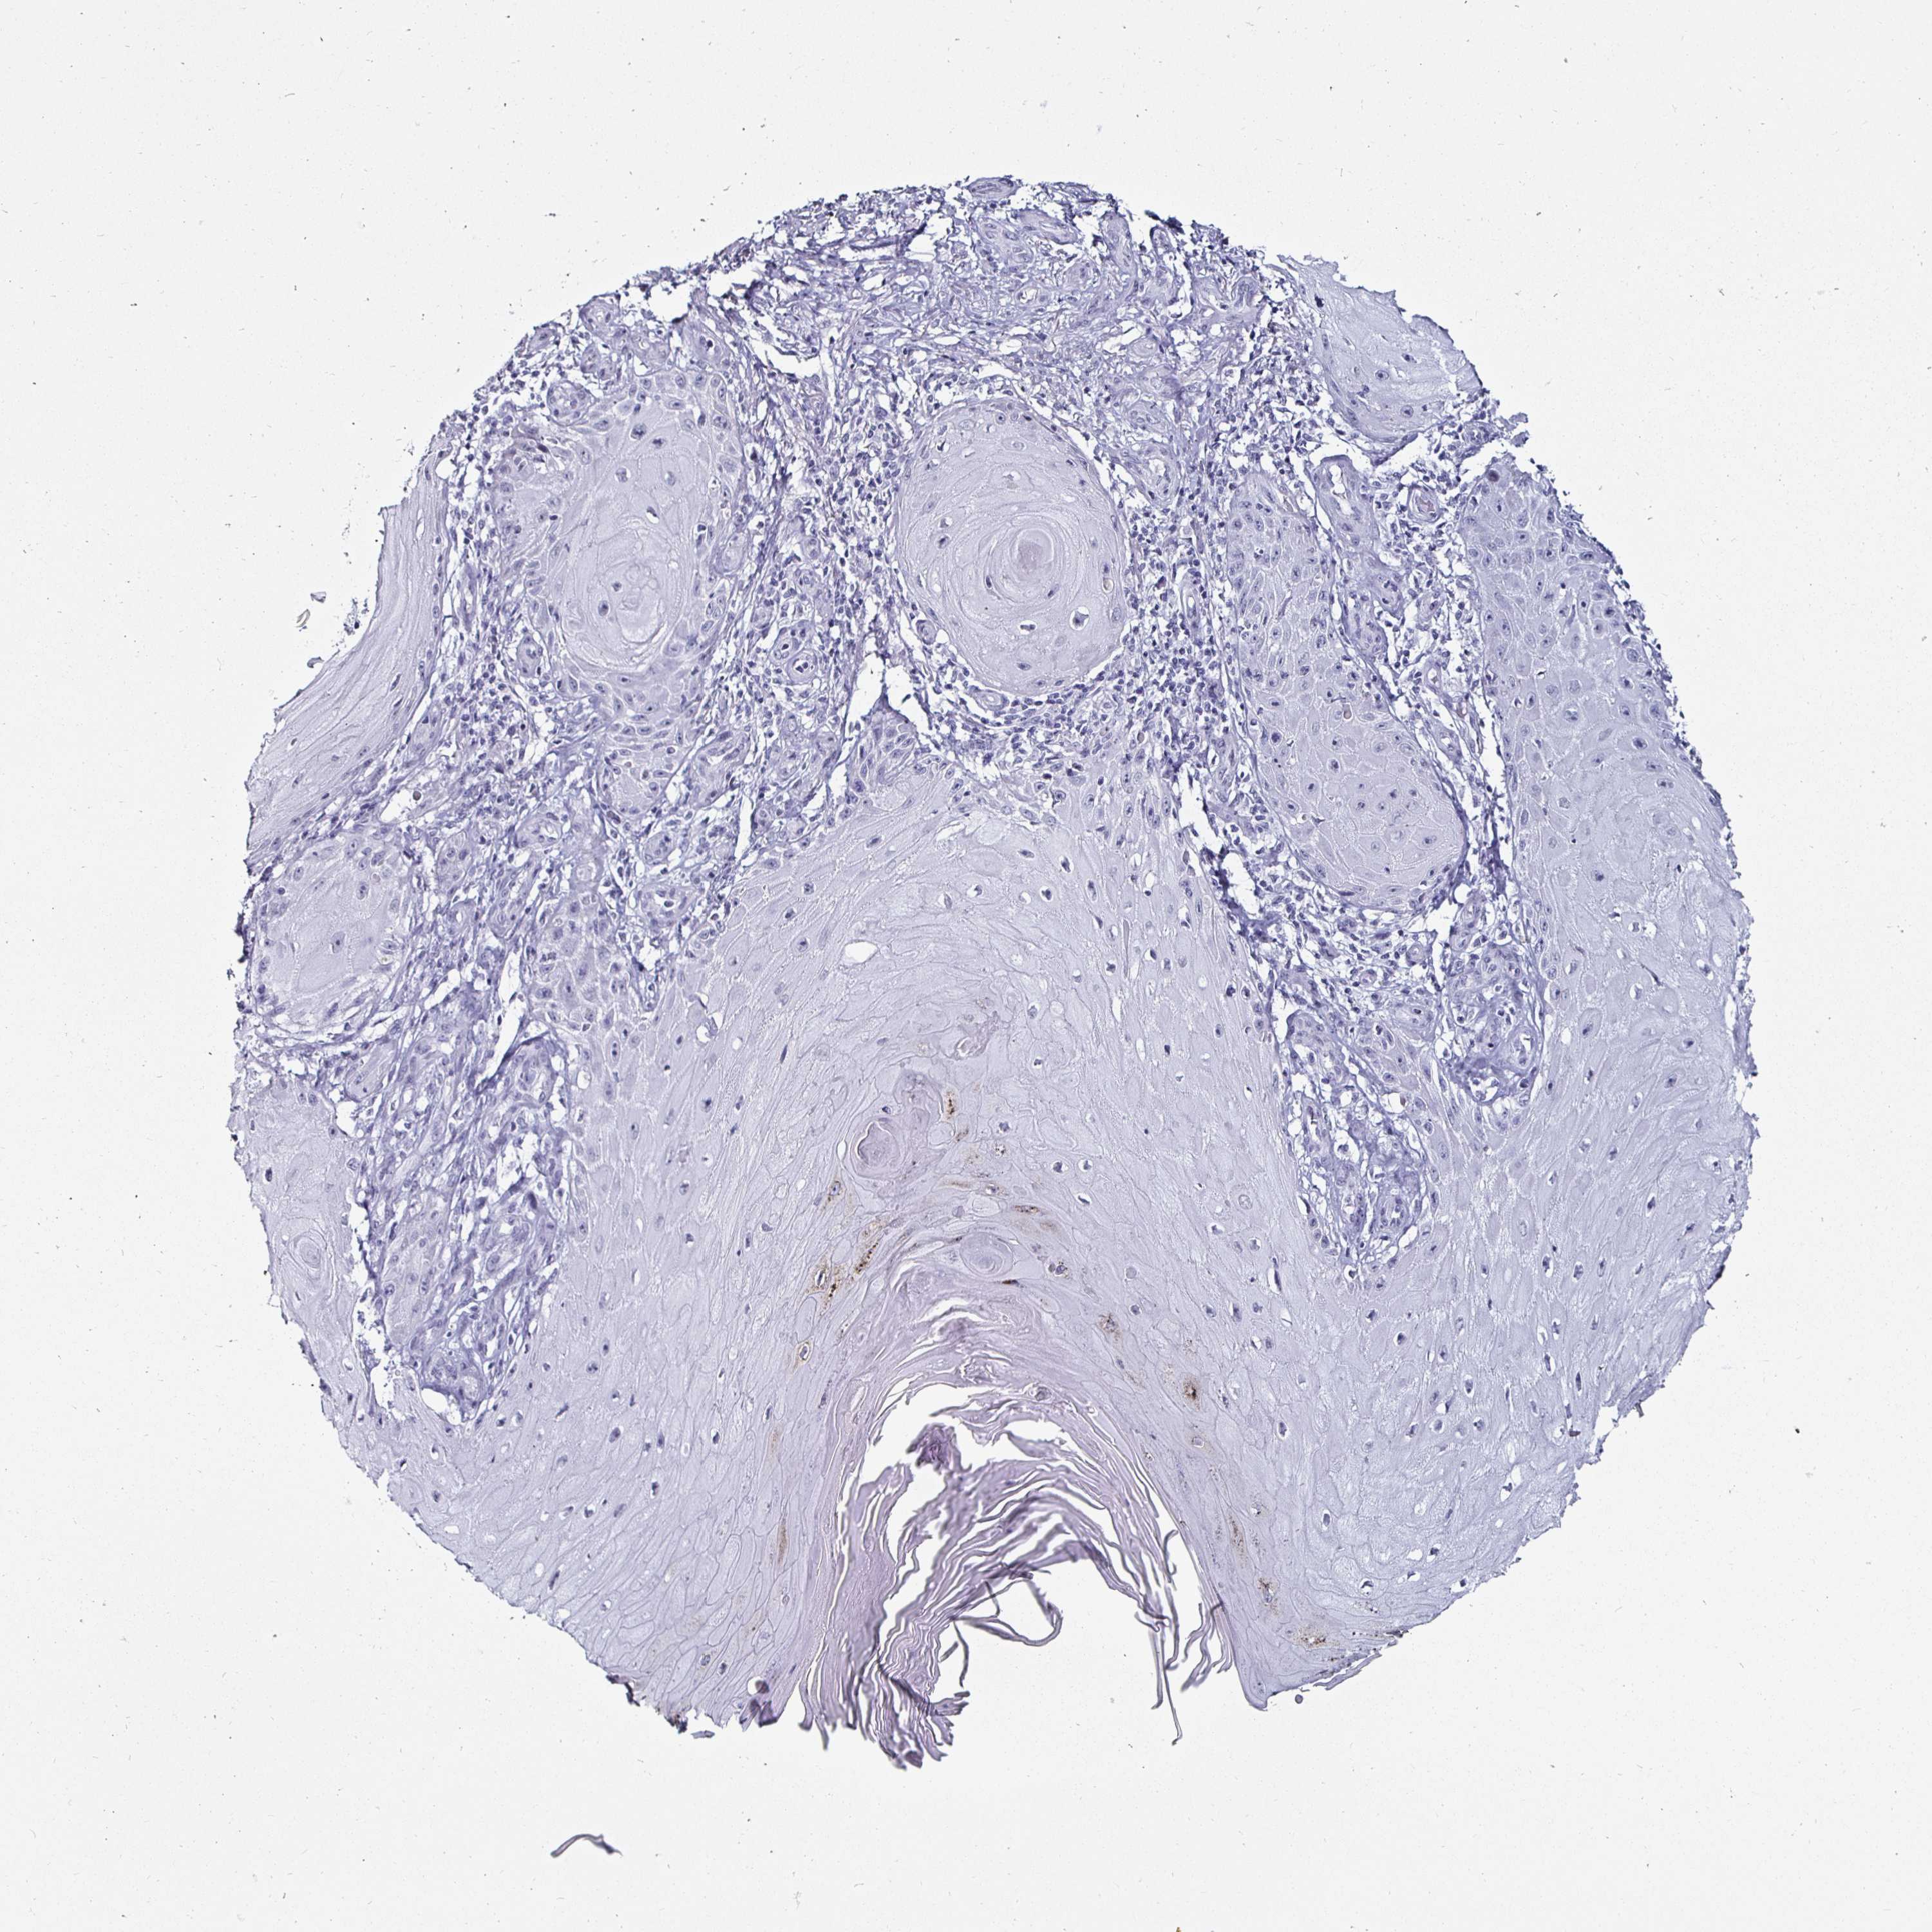

SKIN CANCER - Protein expressioni

A mouse-over function shows sample information and annotation data. Click on an image to view it in a full screen mode. Samples can be filtered based on level of antibody staining by selecting one or several of the following categories: high, medium, low and not detected. The assay and annotation is described here.

Antibody staining in the annotated cell types in the current human tissue is reported as not detected, low, medium, or high, based on conventional immunohistochemistry profiling in selected tissues. This score is based on the combination of the staining intensity and fraction of stained cells.

Each image is clickable and will lead to virtual microscopy that enables deeper exploration of all samples and also displays staining intensity scores, fraction scores and subcellular localization as well as patient and tissue information for each sample.

Antibody HPA034881

Antibody CAB002154

Basal cell carcinoma

Squamous cell carcinoma, NOS